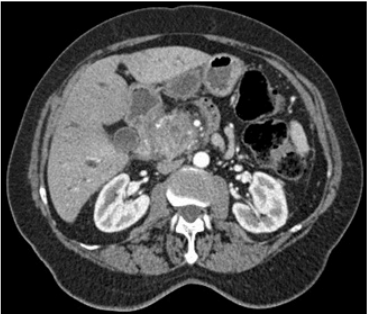

Um paciente de 55 anos de idade iniciou com quadro de icterícia, dor abdominal, colúria e acolia. Perdeu 35 kg em seis meses. Durante o processo de tratamento com quimioterapia, o paciente apresentou, após duas sessões, febre e mal-estar geral, e o hemograma do seguimento do tratamento demonstrava 75 neutrófilos e seu escore de MAASC foi de 15 pontos. A tomografia do paciente, apresentada a seguir, foi inserida para auxiliar no diagnóstico.

Disponível em:<https://www.uptodate.com/>. Acesso em: 27 dez. 2020.

Considerando esse caso clínico, os conhecimentos médicos correlatos e a imagem apresentada, julgue os itens a seguir.